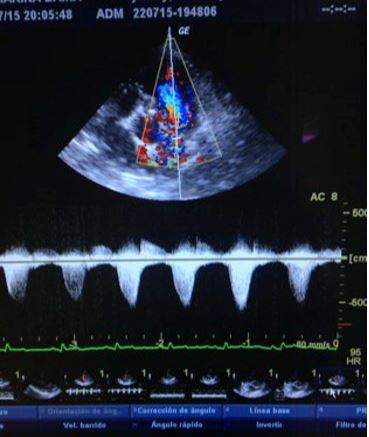

Todo Sobre El Edema Pulmonar En Perros Pronostico Y Tratamiento   - Estenosis pulmonar grave en un cocker spaniel, macho, de 9 anos de edad.

Cardiologia Estenosis Valvula Pulmonar Hvmb   - Mi perro tiene una estenosis pulmonar.